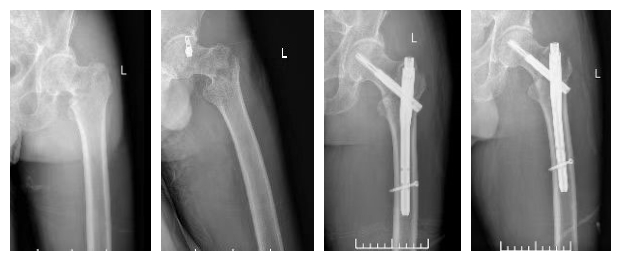

股骨粗隆间骨折微创内固定手术